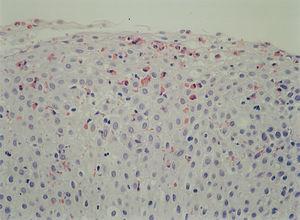

Se instauró dieta de exclusión en todos los pacientes en los que se demostró alguna alergia alimentaria. Tres pacientes recibieron esteroides sistémicos durante 2 meses junto a cromoglicato sódico, que se mantuvo tras el cese de la corticoterapia por 3 meses más, con buena respuesta. En los casos en que se realizó endoscopia de control tras el tratamiento se objetivó una disminución del grado de infiltración eosinofílica (fig. 6). Otros 3 pacientes, recientemente diagnosticados, fueron tratados con montelukast, y desaparecieron los síntomas.

Figura 6. Normalización del infiltrado eosinofílico posterior al tratamiento con corticoides orales en el paciente de la figura 4. (Hematoxilina-eosina, x60.)